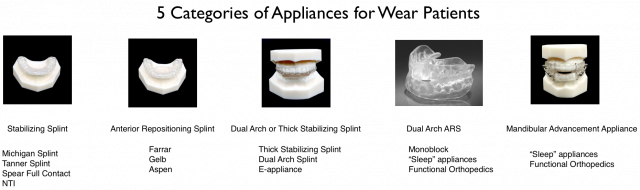

Educators tend to teach the safest splint design. Most institutions choose a stabilizing splint. The design can range from an anterior deprogrammer to a full arch orthosis. Modifications in bite position and disocclusion are possible. Typically, the splint is fabricated with a minimal vertical opening.

It should be noted that the stabilizing splint is only one of the five categories of splints that are utilized in dentistry. Our patients might do much better with a different category. Yet, once we have the laboratory fabricate our go-to appliance, we become financially committed to make it work. Rarely will a dentist say, “That is not working. Let’s make a different design.”

We provide a systematic formula to produce up to five different nightguards for those who do not find resolution with nasal breathing. This is an effort to discern which appliance works best for that unique patient: mandibular flat plane, anterior repositioning, combination splint, monoblock anterior repositioning, or mandibular advancement. All of the provisional splints are made from a single myTAP appliance. The technique will be described in subsequent articles and videos.